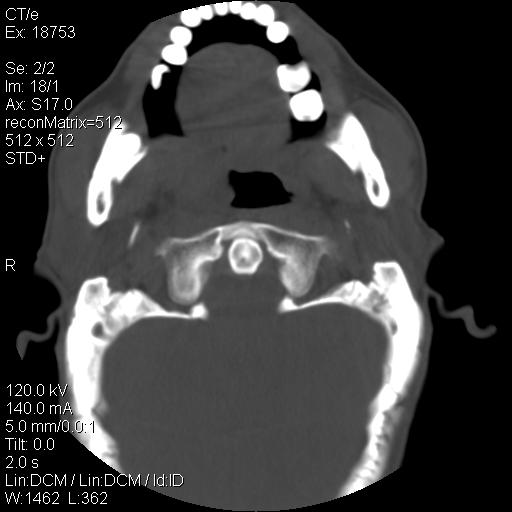

标题: CT21693:男 58岁 右侧咽部疼她2天余 PE:右侧扁桃体肿大 压痛 [打印本页]

标题: CT21693:男 58岁 右侧咽部疼她2天余 PE:右侧扁桃体肿大 压痛

右化脓性扁桃体炎症伴咽后壁脓肿形成.